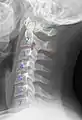

Cervical degenerative changes arise from conditions such as spondylosis, stenosis of intervertebral discs, and the formation of osteophytes. The changes are seen on radiographs, which are used in a grading system from 0–4 ranging from no changes (0) to early with minimal development of osteophytes (1) to mild with definite osteophytes (2) to moderate with additional disc space stenosis or narrowing (3) to the stage of many large osteophytes, severe narrowing of the disc space, and more severe vertebral end plate sclerosis (4).[5][6][7]

X-ray of cervical vertebrae